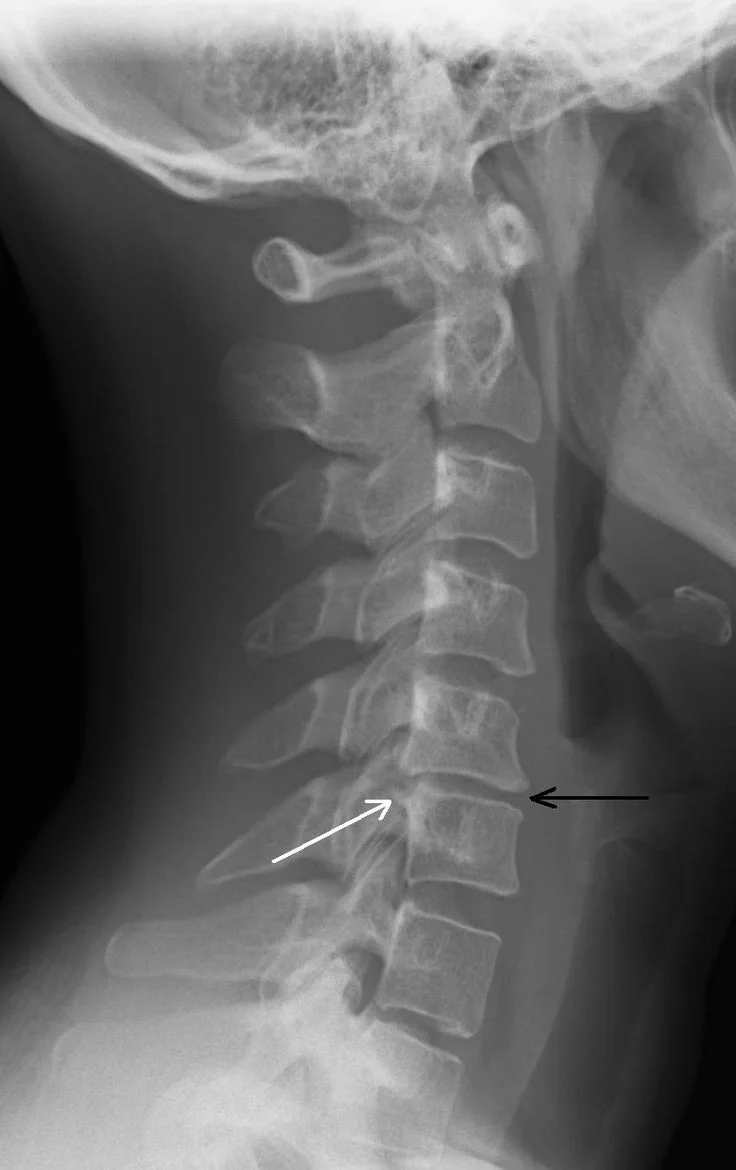

Diagnosis

Diagnosis typically involves a combination of clinical examination and imaging.

Common diagnostic methods include:

- X-ray

- MRI scan

- CT scan

- Neurological examination

MRI is particularly useful because it shows disc hydration, nerve compression, and spinal cord involvement.

Another important finding is that degeneration most frequently affects the C5-C6 spinal level, which bears significant mechanical stress during neck movement. (Frontiers)